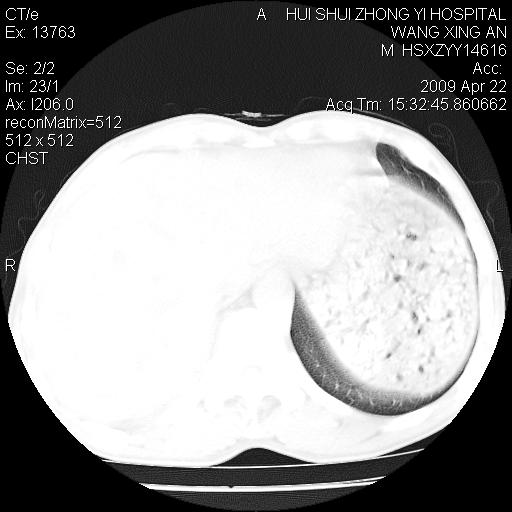

标题: CT19534:患者男、46岁咳嗽、胸痛半月。 [打印本页]

标题: CT19534:患者男、46岁咳嗽、胸痛半月。

考虑---右肺中心型肺癌继发下叶不张,少量胸水。

支持右侧中央型肺ca并右下肺不张、右侧胸腔少量积液。

1、右下肺中央型肺癌并右肺转移,右肺下叶不张。(右肺有结节影)。

2、右中上肺陈旧性肺结核(因为大多为纤维灶)。

3、右侧胸腔积液。

1、右下肺中央型肺癌并右肺转移,右肺下叶不张。(肿块围绕右肺下叶支气管生长,致管腔闭塞右肺下叶不张;右肺有结节影)。

2、右侧胸腔积液。

3、右中上肺陈旧性肺结核(右肺见纤维化病灶及点状钙化)。

1、右下肺中央型肺癌并右肺转移,右肺中下叶不张。(右肺有结节影)。胸骨转移

1)右肺中间段支气管癌并右肺下叶肺不张。2)右肺上叶、两肺下叶背段感染性病变。3)右侧少量胸腔积液。